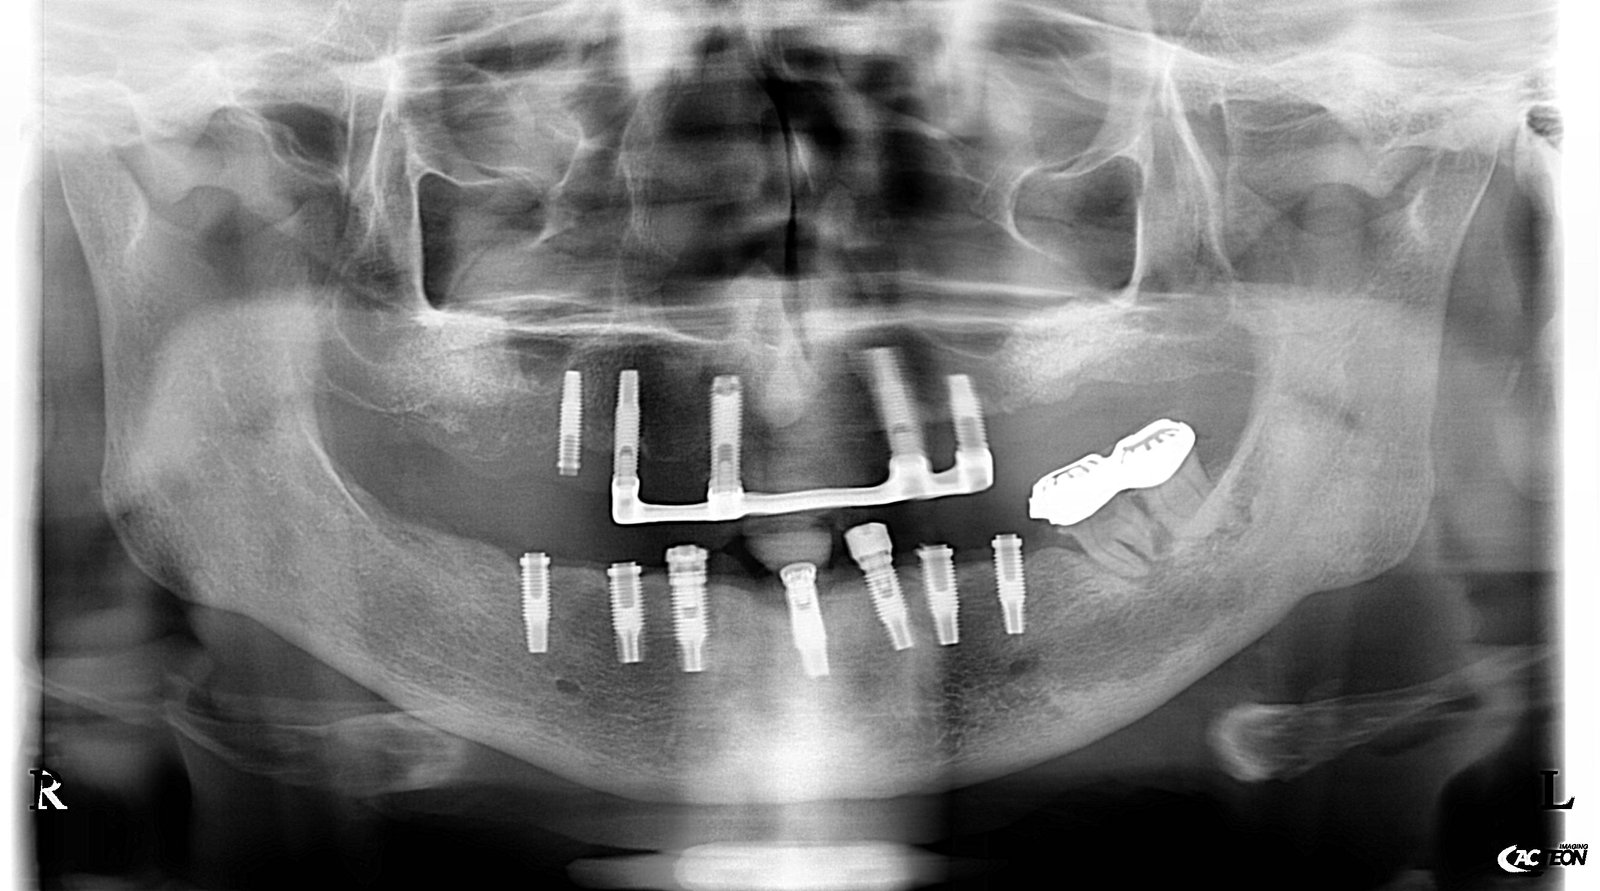

Paciente extranjero que acude por rotura de prótesis sobre los implante y realizar reendodoncia del 21, no consigo saber que implantes son y el paciente tampoco aporta información.

¿Saber que tipo de implantes son? Nos gustaría saber tipo de implantes que son puestos en Estados Unidos (USA). Adjuntamos radiografías, a la espera de que nos podáis ayudar en [...]

Están colocados 4 implantes en zonas de 3.4, 3.2, 4.3, 4.5, contienen un pilar intermedio que atornilla a la prótesis con un tornillo de 1.25 y dicho pilar intermedio se [...]